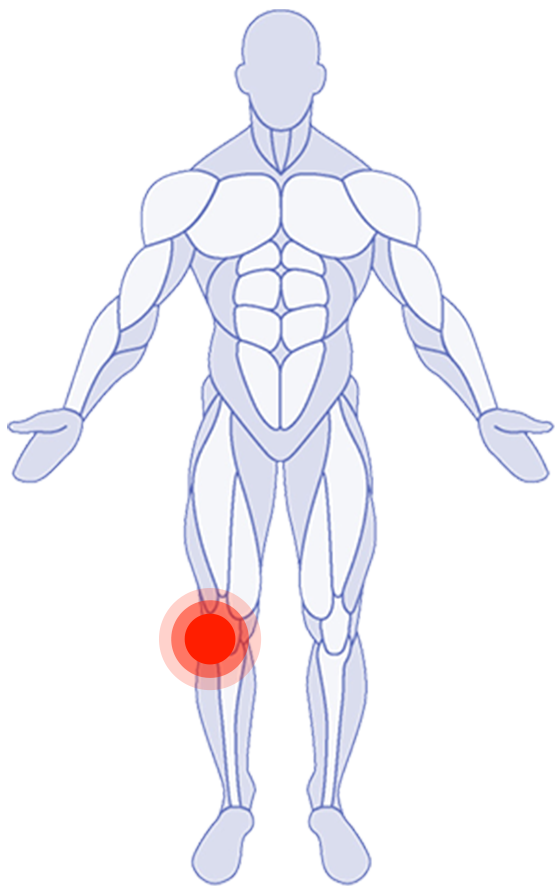

Where do you need attention?